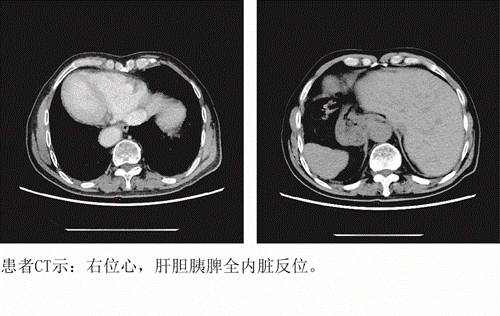

患者周先生,72岁,因“大便性状、习惯改变,便中带血1年”至临床医学院/附属医院就诊,通过肠镜及病理检查显示,为直肠恶性肿瘤;胸、腹部CT显示,全内脏镜面转位。面对如此罕见病例,普外科胃肠外科孙胜主任、宋志主治医师、谈运长主治医师带领团队围绕该患者解剖的变异、术式及围手术期处理进行了细致讨论,制定了严密的手术计划及应急预案。经过充分商讨,决定为患者行腹腔镜下直肠癌根治术,在麻醉科和手术室等全力配合下,经过一个半小时,手术顺利完成。